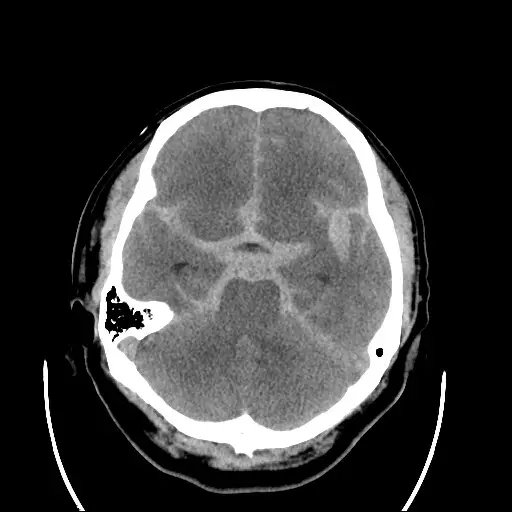

本題附圖為腦部非顯影電腦斷層(non-contrast CT of brain),軸切面(axial view)。影像重點所見:

- 高密度出血灶:左側顳葉內側/Sylvian 裂區域可見明顯高密度(白色)不規則出血,形狀不規則,提示腦內出血合併蜘蛛膜下腔出血(subarachnoid hemorrhage, SAH)的可能。

- 腦室系統:腦室形態大致正常,無明顯腦積水(hydrocephalus)。

- 中線結構:中線無明顯偏移。

- 對側腦實質:右側腦實質密度均勻,無異常出血或梗塞病灶。

臨床意義:CT 上 Sylvian 裂或基底池出現高密度血液,結合患者突發劇烈頭痛、動眼神經麻痺,高度懷疑後交通動脈瘤(posterior communicating artery aneurysm)破裂所致 SAH。非顯影 CT 對急性 SAH 敏感性在 6 小時內約 98%,但不能確定動脈瘤位置,因此確診及定位需接續腦血管造影。